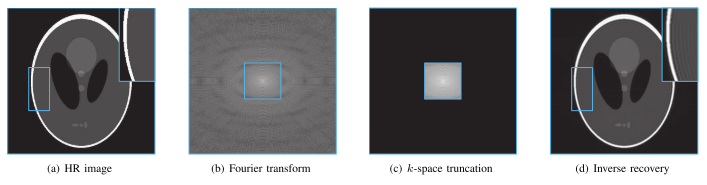

- LR图像:根据双三次下采样和k空间截断(HR 图像首先通过离散傅里叶变换 (DFT) 转换为 k 空间,然后沿高度和宽度方向进行截断)生成的。